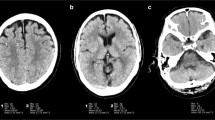

The overall image quality, noisiness, and gray–white matter sharpness were significantly better with DLR than with conventional or original reconstructions (all P < 0.001, post hoc Dunn’s pairwise comparisons). The conventional reconstruction showed better overall image quality, noisiness, and gray–white matter sharpness scores compared to the original image (all P < 0.05, except for image noise score of radiologist 1, post hoc Dunn’s pairwise comparisons) (Fig. 1).

Axial T2-weighted images of a 2-month-old boy with three different reconstructions (a original reconstruction; b conventional reconstruction; c deep learning reconstruction). Deep learning reconstruction shows lower noise and better image quality than the other two reconstructions. Motion artifacts are unaffected with the deep learning reconstruction (arrows)

Motion and pulsation artifacts showed no significant difference among three reconstructions (Fig. 1). No identifiable artifacts related to DLR were reported.